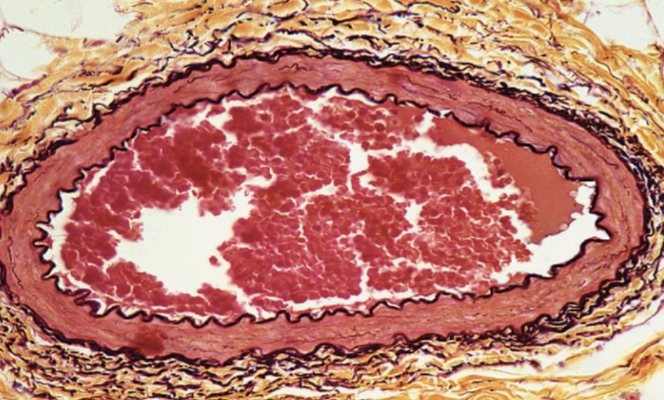

Identifique tipo de tejido conectivo

elastico

Indique sitio anatómico dónde se encuentra

vasos sanguineos